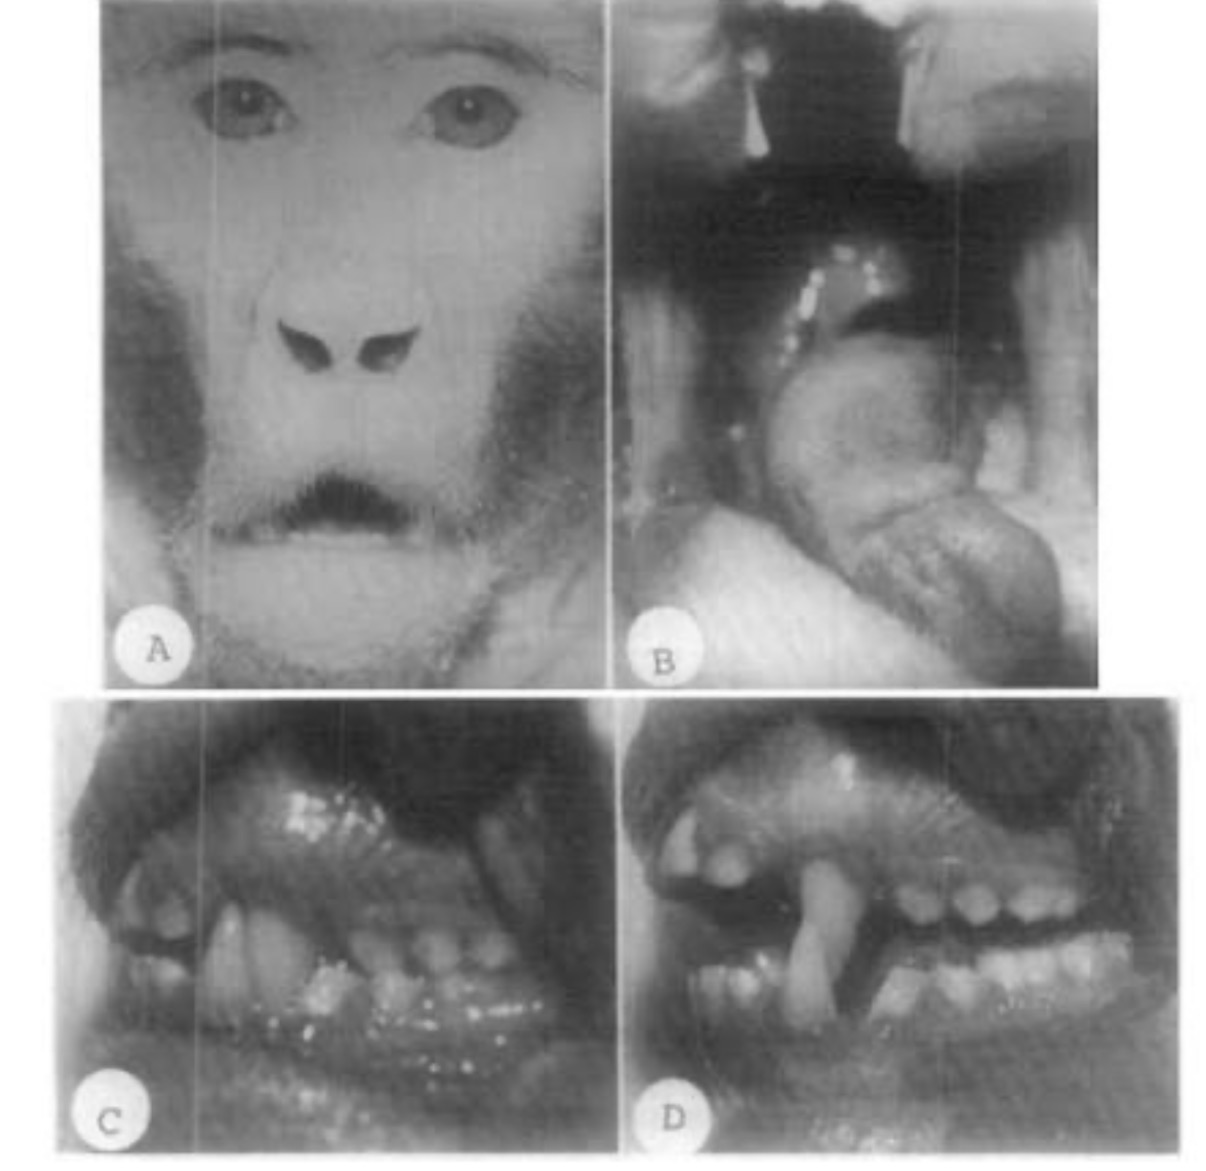

Look into this study of improper habits on a monkey.

View attachment 4639996

Downward growth and recession of maxilla/mandible isn’t genetic, only bad habits.

Almost all babies are born with correct growth and get destroyed over time.

Look into this study of improper habits on a monkey.

View attachment 4639996